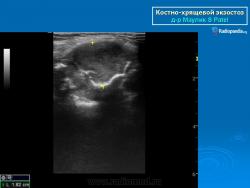

Локализация остеохондромы: частота поражения отдельных костей различна; нижний коней бедренной кости, верхние отделы плечевой и большеберцовой костей поражаются более чем у половины больных. На всем протяжении остеохондрома покрыта надкостницей. Она может быть обнаружена и в других костях, за исключением костей лицевого черепа. Все же поражение костей позвоночника, кистей рук и стоп встречается редко. При рентгенологическом исследовании видна типичная картина узкого или широкого выроста вблизи эпифизарной части пораженной кости. Обычно плотность узла неоднородная, имеются многочисленные плотные участки, соответствующие обызвествленным хрящевым долькам. Хрящевая «шапочка» большей частью не определяется, поскольку хрящ остается необызвествленным. Она может быть выявлена только при магнитно-резонансной томографии.